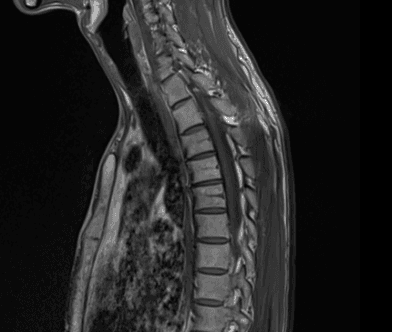

이런 경우에 골절이 아닌지 오해하시는 경우가 많은데 골절이 아닙니다.

골절의 경우에는 T1 영상에서 조영이 떨어지고 fat suppression T2 영상에서 조영이 증가하는 소견을 확인해야합니다.

골절이 아니면 왜 저렇게 보이는지 까지는 제가 잘 모르지만 저 소견을 이상소견으로 보이는 않습니다.